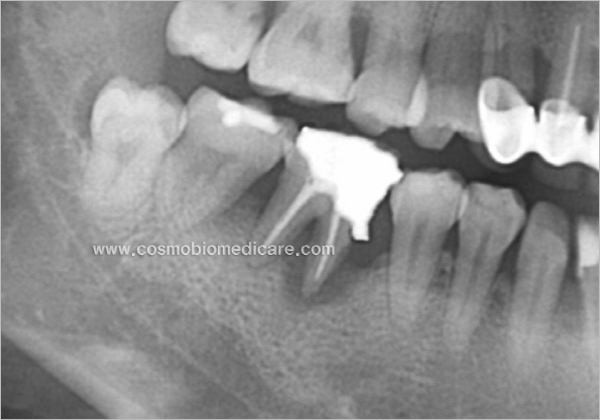

Clinical Cases

• Case1

• Case2

• Case3

• Case4

• Case5

• Case6

• Case7

• Case8

• Case9

• Case10